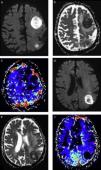

El patrón ordenado o en “doble anillo” de los productos de fagocitosis que determinan la presencia de este artificio es muy útil en el diagnóstico diferencial de las lesiones con patrón de realce anular, sobre todo con lesiones tumorales de alto grado con necrosis, como el glioblastoma multiforme14 (fig. 2).

Absceso cerebral bacteriano inespecífico, confirmado luego del drenaje quirúrgico. Los cortes seleccionados de la RM en el plano axial demuestran la utilidad de (a) la secuencia de susceptibilidad magnética, (b) la SE ponderada en T1 con contraste, (c) la difusión y (d) el mapa de ADC. En la susceptibilidad magnética se identifica el aspecto típico de la cápsula bacteriana con un patrón en diana o de doble pared, debido al depósito ordenado de productos de degradación de la hemoglobina. La lesión presenta el típico realce en anillo fino, regular, completo y sin nódulos, con un centro necrótico con un intenso fenómeno de restricción en la difusión.

Se ha establecido la presencia de un intenso fenómeno de restricción en el centro de los AC bacterianos inespecíficos, que ha sido relacionada con la viscosidad del pus y su escasa celularidad18,19(fig. 2).

La presencia de restricción en una lesión con realce en anillo permite establecer el diagnóstico de AC bacteriano (con niveles de especificidad cercanos al 100%) y lo diferencia, sobre todo, de lesiones tumorales con necrosis o contenido quístico18,20,21 (fig. 4). Incluso, este hallazgo se ha señalado como patognomónico del AC, a pesar de que puede encontrarse en otro tipo de lesiones, como algunas metástasis con contenido de alta viscosidad o glioblastomas con hemorragia22.